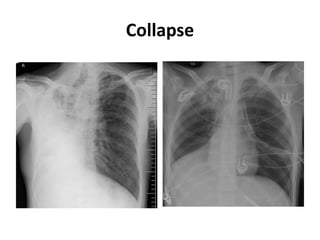

Collapse